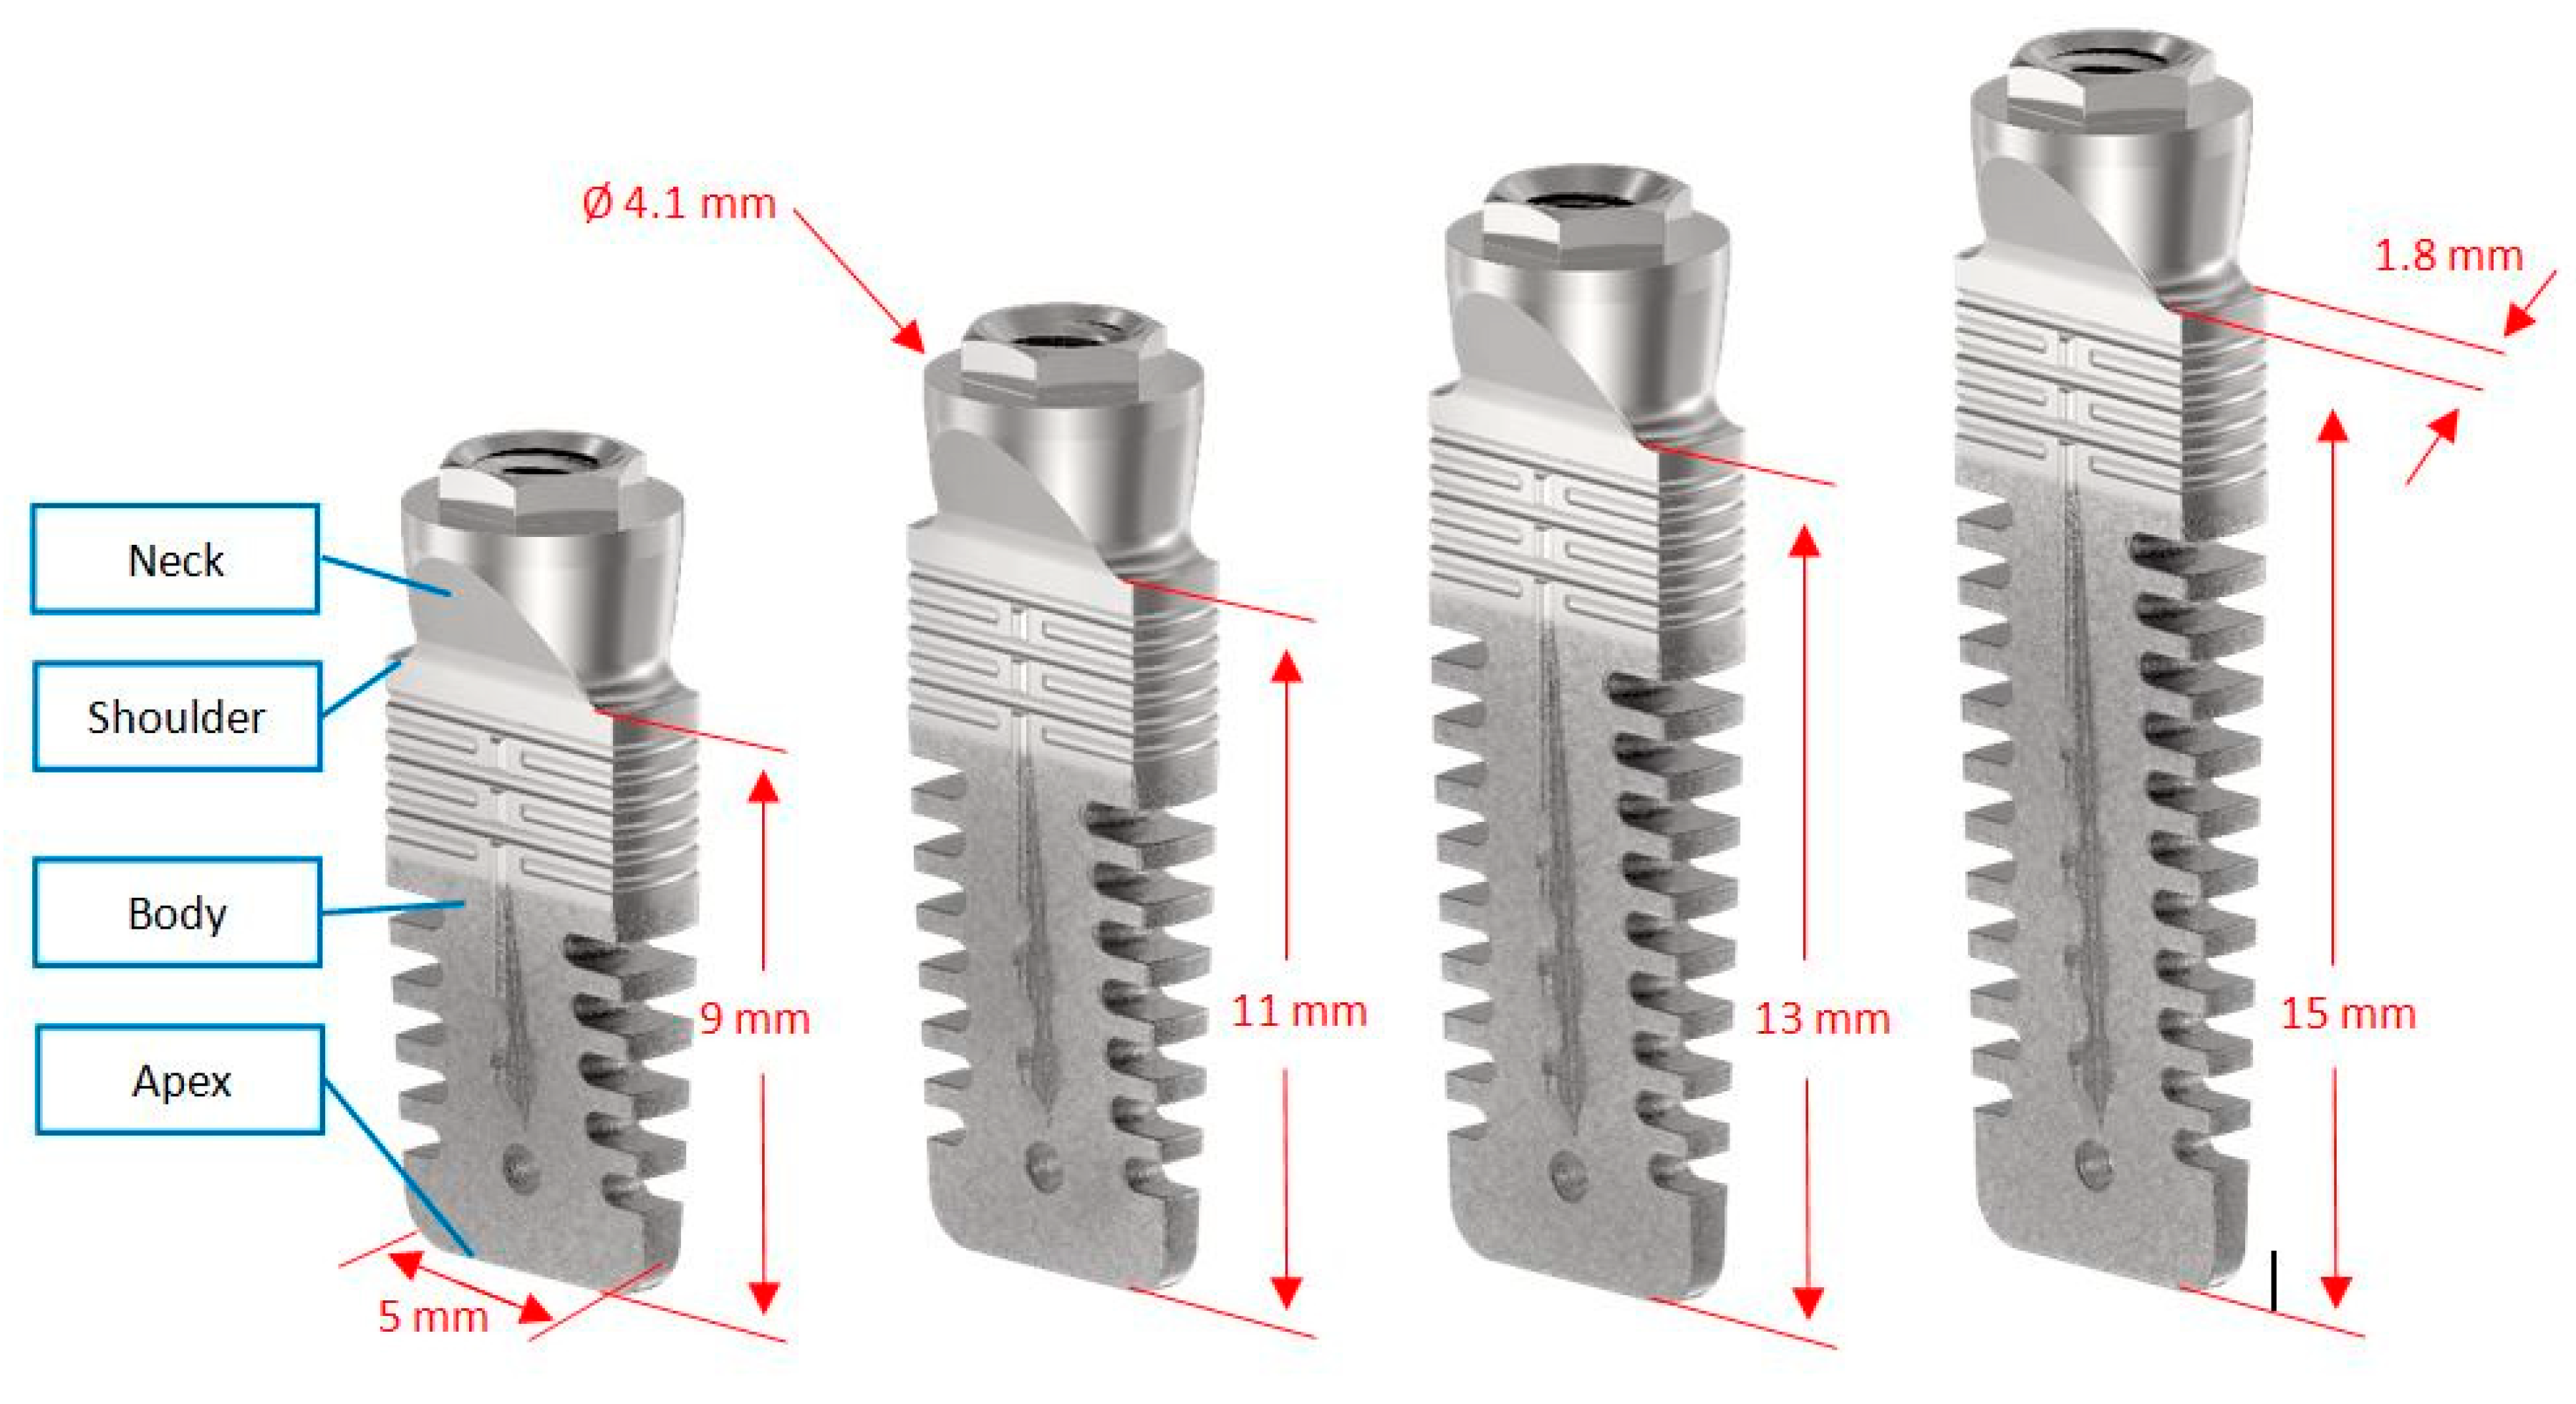

2.2. Surgical and Prosthetic Procedures

| Implant Length | 9 mm (19)/11 mm (40) |